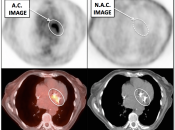

Value of Non-Attenuation Corrected (NAC) Images

Resolving Attenuation Correction Artifacts:

The CT images obtained during an exam are not only used for “anatomic” interpretation. They are also used for “attenuation correction” (AC) of the PET images, generating the much more useful AC PET images used for interpretation.

Unfortunately, attenuation correction of PET images can result in falsely elevated metabolic activity in regions of high CT density (e.g. metallic devices, oral contrast, calcification).

In such cases, these areas must be reviewed on the NAC (non-attenuation correction) images. If these regions are not also hypermetabolic on the NAC images, then their apparent increased FDG-uptake on the AC images is artefactual.

This phenomenon is almost exclusively seen with older PET/CT scanners, as most modern scanners utilize newer algorithms that do not “over-correct” in these areas of increased density.